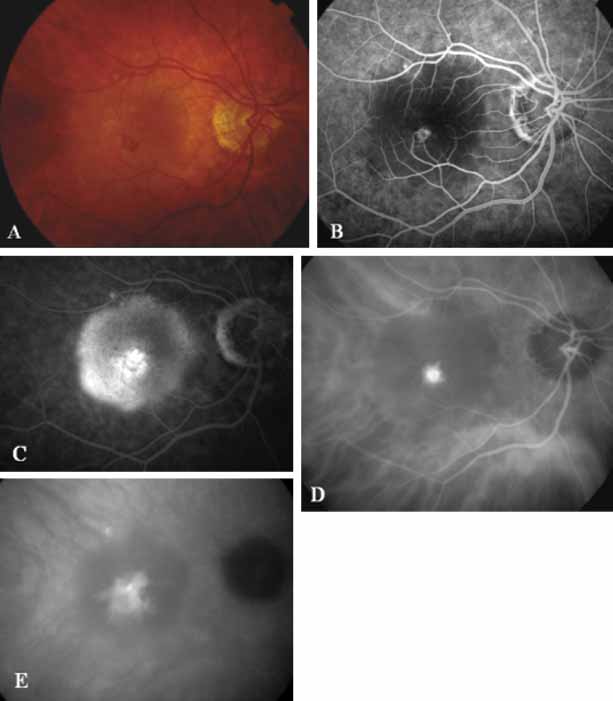

In a landmark article, Yannuzzi and associates18 demonstrated that ICG videoangiography was extremely useful in identifying well-demarcated localized areas of neovascularization in what had been classified as occult CNV by standard fluorescein angiography.19–24 In this study, 39% of 129 patients with “occult CNV” originally diagnosed as determined by fluorescein angiography were given a revised diagnosis of “well-defined neovascular lesions” based on the information obtained from the ICG study (Fig. 1). One study revealed that approximately 40% of patients with occult CNV diagnosed actually presented with early, well-defined focal areas of fluorescence on ICG videoangiography.25 They further defined two potential subgroups of occult CNV: those with and those without serous pigment epithelial detachments (PEDs) accompanying the occult neovascular process. They also pointed out that ICG angiography offered a potential advantage in identifying neovascular lesions when there was clinical evidence of recurrent CNV after previous laser photocoagulation treatment.

Subsequently, Yannuzzi and colleagues25 and Guyer and associates26 evaluated the usefulness of ICG angiography in identifying localized areas of CNV in patients with occult CNV with or without a serous PED. In a careful evaluation of more than 680 patients, they identified 22% of patients with localized lesions that might be amenable to laser therapy—lesions that would otherwise be classified as untreatable based on guidelines for laser photocoagulation (Figs. 2 and 3). As a result of this improved imaging technique, as many as two to three times the number of patients would have been potentially eligible for laser treatment than would have been treatable based on fluorescein angiography alone.

An important report by Chang and co-workers27 lends support to the rationale for interpreting the hyperfluorescence seen on ICG angiography as CNV. In this clinicopathologic study, a patient was identified who had experienced subretinal hemorrhage with early signs of occult CNV on fluorescein angiography (Fig. 4A). Fluorescein angiography demonstrated blocked fluorescence (Fig. 4B). The ICG study, however, demonstrated late staining in a well-circumscribed fashion, which the authors interpreted as a “plaque” of occult CNV (Fig. 4C). When the patient died, this area was evaluated and studied histopathologically and compared with the picture seen on ICG angiography. The area of hyperfluorescence on the ICG study corresponded precisely to a thin layer of fibrovascular tissue beneath the pigment epithelium and neurosensory retina, confirming that the late-staining tissue imaged with ICG angiography was truly a neovascular membrane (Fig. 4D).

With this clinical diagnostic and histopathologic information available, pilot studies were performed to determine the practicality of using ICG angiographic guidance in the treatment of occult CNV. Slakter and associates28 performed laser photocoagulation treatment on 79 eyes with occult CNV. The occult CNV was successfully eliminated in 57% of patients who underwent ICG-guided treatment (Figs. 5 and 6). The authors found the success rate to be higher (66%) for patients with CNV not associated with PEDs than for those with PEDs (43%). Visual acuity improvement or stabilization was achieved in 57% of all patients. Recurrences were more frequent and more difficult to control in those patients who had associated PEDs on initial clinical presentation. Additional independent studies have reported similar diagnostic and treatment outcomes with the use of ICG angiography in patients with occult CNV.29,30